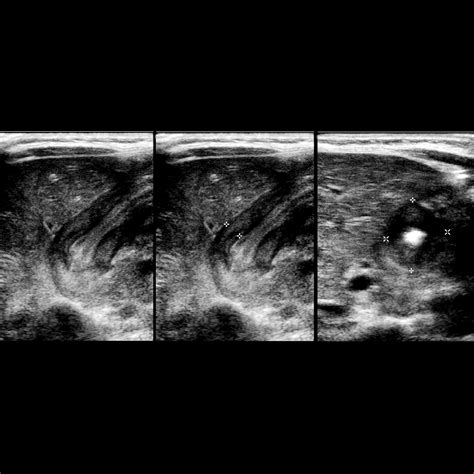

• Pyloric Stenosis: This is a condition where the muscle at the outlet of the stomach thickens, making it difficult for food to pass into the small intestine. It is a medical emergency and requires immediate attention.